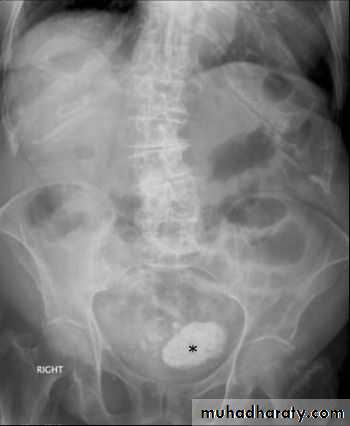

Abdominal calcifications

Assessment of the shape and pattern of abdominal calcification will usually limit the diagnosis to one or two choices. Calcification in the abdomen are likely to be :1. Pelvic vein phleboliths: very common, may be mistaken for urinary stones & fecoliths

13. Renal stones and other calcifications of the urinary tract